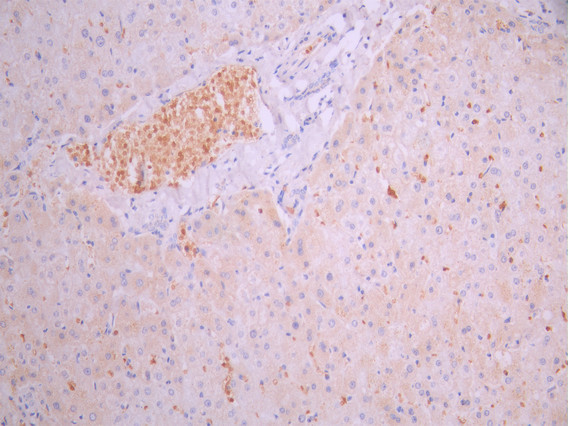

IHC image of CSB-RA007743MA1HU diluted at 1:50 and staining in paraffin-embedded human liver tissue performed on a Leica BondTM system. After dewaxing and hydration, antigen retrieval was mediated by high pressure in a citrate buffer (pH 6.0). Section was blocked with 10% normal goat serum 30min at RT. Then primary antibody (1% BSA) was incubated at 4°C overnight. The primary is detected by a Anti-Human lgG, Fcy Fragment Specific labeled by HRP and visualized using 0.05% DAB.